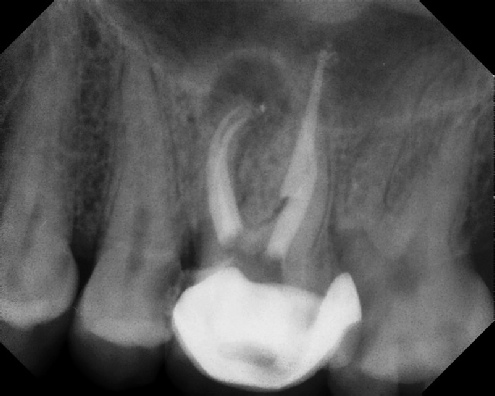

Root Canal Retreatment - Meriden 8 mos. recall Post-op Pre-op